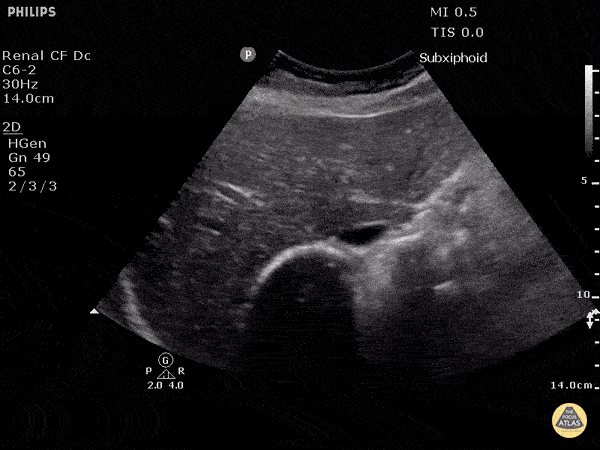

View: Unspecified Parasternal Long Axis Parasternal Short Axis Apical Four-Chamber Subcostal Four-Chamber Subcostal Inferior Vena Cava Right Upper Quadrant Left Upper Quadrant Suprapubic Longitudinal Suprapubic Transverse Subxiphoid Anterior Thoracic Phrenic